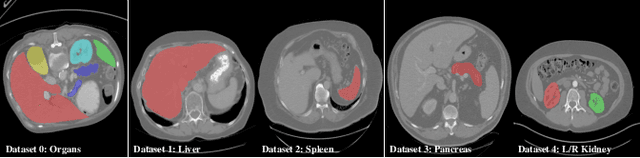

Abstract:There exists a large number of datasets for organ segmentation, which are partially annotated and sequentially constructed. A typical dataset is constructed at a certain time by curating medical images and annotating the organs of interest. In other words, new datasets with annotations of new organ categories are built over time. To unleash the potential behind these partially labeled, sequentially-constructed datasets, we propose to incrementally learn a multi-organ segmentation model. In each incremental learning (IL) stage, we lose the access to previous data and annotations, whose knowledge is assumingly captured by the current model, and gain the access to a new dataset with annotations of new organ categories, from which we learn to update the organ segmentation model to include the new organs. While IL is notorious for its `catastrophic forgetting' weakness in the context of natural image analysis, we experimentally discover that such a weakness mostly disappears for CT multi-organ segmentation. To further stabilize the model performance across the IL stages, we introduce a light memory module and some loss functions to restrain the representation of different categories in feature space, aggregating feature representation of the same class and separating feature representation of different classes. Extensive experiments on five open-sourced datasets are conducted to illustrate the effectiveness of our method.

Abstract:There exists a large number of datasets for organ segmentation, which are partially annotated, and sequentially constructed. A typical dataset is constructed at a certain time by curating medical images and annotating the organs of interest. In other words, new datasets with annotations of new organ categories are built over time. To unleash the potential behind these partially labeled, sequentially-constructed datasets, we propose to learn a multi-organ segmentation model through incremental learning (IL). In each IL stage, we lose access to the previous annotations, whose knowledge is assumingly captured by the current model, and gain the access to a new dataset with annotations of new organ categories, from which we learn to update the organ segmentation model to include the new organs. We give the first attempt to conjecture that the different distribution is the key reason for 'catastrophic forgetting' that commonly exists in IL methods, and verify that IL has the natural adaptability to medical image scenarios. Extensive experiments on five open-sourced datasets are conducted to prove the effectiveness of our method and the conjecture mentioned above.